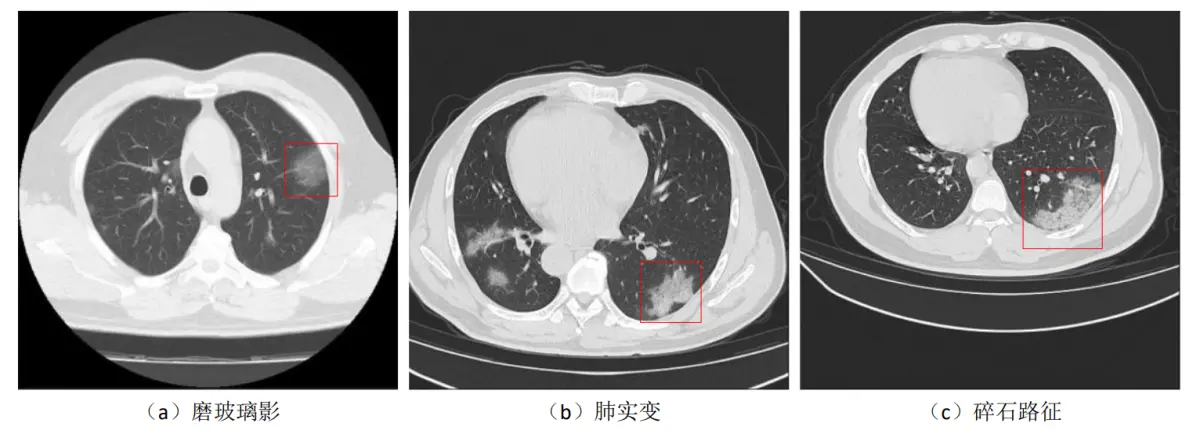

7.CT 图像上的 COVID-19 病灶特征

一般情况下,COVID-19病灶区域首先表现为肺泡中积聚较多液体,由于液体密度比空气大,因此在CT图像中呈现为半透明糊状的灰色阴影,也称为“磨玻璃影”,如图(a)红框区域所示。另外一些较严重的肺部感染病例中,由于越来越多的液体积聚在肺叶内,密度逐渐增大,导致在CT图像中磨玻璃影逐渐进展为实心白色样的“肺实变”,如图(b)红框区域所示。在更为严重的一些病例中,由于肺小叶壁间质肿胀,肺泡壁增厚,其较大的密度导致在CT图像中看起来就像一条条白线,这些白线将肺实变或者模糊的磨玻璃影分隔开,整体看上去犹如碎石铺成的道路,也因此称为“碎石路征”,如图(c)所示。在COVID-19感染者的CT图像中,从时间范围来看,磨玻璃影一般是首发影像特征,另外两种特征随后单个出现或者同时出现,从空间范围来看,这些影像特征一般遍布双肺多个肺叶,更常见于双肺外围,对于轻症患者或者正在痊愈的患者,这些特征也可能仅累及单个肺叶,COVID-19患者的患病严重程度和双肺的改变程度成正比。从图中的三种病灶表征图像来看,仅从灰度上不能将病灶区域和其他肺部组织进行区分,而且不同的病变在纹理、位置上均有较大区别,手工构造特征难以应对这些情况,因此COVID-19病灶分割任务更适合采用基于

需要说明的是,虽然CT图像中出现的以上病灶表征对于COVID-19的敏感性很高,但上述影像特征:磨玻璃影、肺实变、碎石路征,也可能在由其他病毒(如流感病毒、腺病毒)引起的肺炎中看到,另外在一些非感染性疾病中也可能出现此类影像。CT中的病灶区域表征对COVID-19敏感性虽然很高,但其特异性较低,如果直接将CT应用于COVID-19患者筛查,那么对发现有这些影像表现的患者应进一步进行全面的检查才能确认诊断结果。但在通过实验室检查明确病因之前,首先隔离这些有典型CT表现的患者,可以有效阻止潜在病毒的进一步传播,另外由于COVID-19患者的患病严重程度和双肺的改变程度成正比,在COVID-19患者的临床监测过程中,对CT图像中的磨玻璃影、肺实变、碎石路征进行分割,可以有效的量化患者的病情严重程度,同时为医生提供更好的可视化结果。